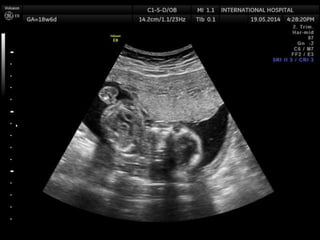

Amniotic band sequence:

Amniotic band sequence refers to a highly variable

spectrum of congenital anomalies that occur in

association with amniotic bands

Amniotic band sequence: Amnioticband sequence refers to a highly variable spectrum of congenital anomalies that occur in association with amniotic bands The estimated incidence of ABS ranges from 1:1200 to 1:15,000 in live births, and 1:70 in stillbirths

Anomalies include: Craniofacial abnormalities— eg, encephalocele, exencephaly, clefts, which are often in unusual locations; anencephaly. Body wall defects (especially if not in the midline), abdominal or thoracic contents may herniate through a body wall defect and into the amniotic cavity. Limb defects — constriction rings, amputation, syndactyly, clubfoot, hand deformities, lymphedema distal to a constriction ring. Visceral defects — eg, lung hypoplasia. Other — Autotransplanted tissue on skin tags, spinal defects, scoliosis, ambiguous genitalia, short umbilical cord due to restricted motion of the fetus